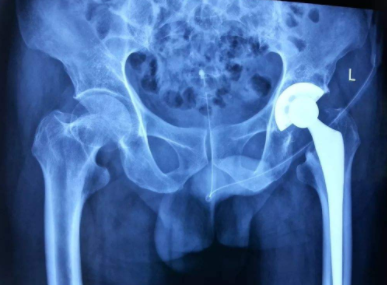

股骨头坏死三期可以不手术吗?徐学成专家提醒您会有

河南股骨头坏死医院介绍股骨头坏死可以说是特别常见的一种疾病,这种疾病的发生一般多是由…[详情]

股骨头坏死二期可以治好吗?徐学成医生为你介绍治疗

河南治疗股骨头坏死医院介绍股骨头坏死主要是分为四期,一期到二期相对来说坏死不涉及受力…[详情]

股骨头缺血性坏死怎么办?徐学成医生提醒您一定要进

郑州股骨头坏死病医院介绍股骨头缺血坏死在医院里如果得到确诊,一般可以分为早期、中期、…[详情]